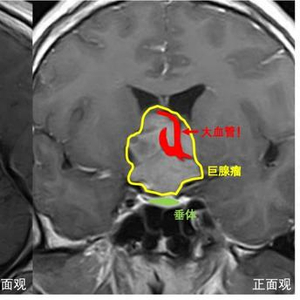

这是一颗足足有5公分大的脑瘤,更不巧的是,肿瘤形态并不规则,呈菜花状,侵犯脑内的多个腔隙,向前突向前颅底,向后生长进入脚间池,向上方长入三脑室,包绕了大脑前动脉,用“张牙舞爪”来形容真的一点也不过分。不仅如此,肿瘤周围还有视神经、下丘脑、颈内动脉等多个重要的血管和神经,手术犹如在刀尖上跳舞,稍有不慎便会“万劫不复”。

此次采用的手术方案是内镜经鼻联合开颅手术切除肿瘤,该手术方案作为“上海市可开展的新增医疗技术”由华山医院神经外科王镛斐团队率先申报,是目前国际最先进的处理复杂脑肿瘤的手术方法。以往对于此类肿瘤,都是采取先开颅手术,过一段时间后再进行经鼻手术切除,这样做病人需要经受两次手术,时间、精力和财力投入都比较大,而且开颅手术会造成疤痕粘连,为再次经鼻手术切除肿瘤造成一定困难。此次采用的“上下联合入路”同时需要两组手术医生,分别采取开颅和内镜经鼻的方法切除肿瘤,两组医生相互配合下可以实现优势互补,能最大程度地保证安全地切除肿瘤。

上午9:00,一切准备就绪,手术按照既定规划有条不紊开始。摆放好位置后,王镛斐负责内镜经鼻手术,从下方捣毁肿瘤根基,寿雪飞副教授负责开颅手术,从上方挖取肿瘤顶部。幸运的是,在药物治疗后,肿瘤血供明显减少,这让医生在切除肿瘤时更好地控制出血量,避免大量失血。对于钻进各腔隙内不易切除的肿瘤,寿雪飞通过将其向下推挤,使其暴露在视野内,王镛斐则趁机将此部分肿瘤从下方挖出,完美诠释了什么是“精诚合作”。最终,“上下会师”,开颅组和经鼻组的器械相遇,意味着肿瘤已经全部切除。